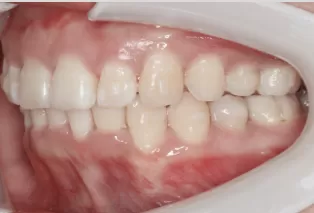

Female, 25 years old. Chief complaint: protruding and misaligned teeth, requiring orthodontic treatment.

Intraoral photos